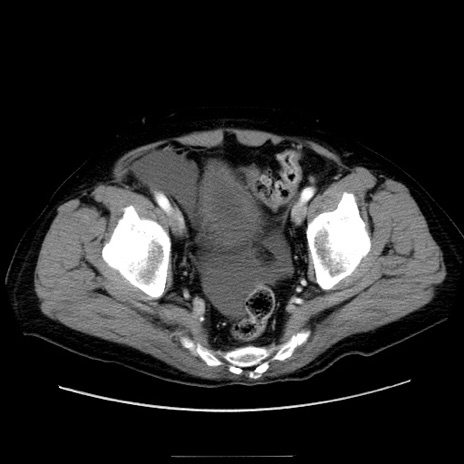

冠状断像

【症例】80歳代男性

【現病歴】約6時間前から臍下部痛が出現。次第に腹部膨隆・背部痛も生じてきたため来院。背部痛の場所は変化しない。

【身体所見】意識清明、BT 36.3℃、BP  131/87mmHg、P 87bpm、SpO2 100%(RA)、臍周囲自発痛・圧痛あり、反跳痛なし、自発痛部位に一致して板状硬あり、腹部膨隆、腸雑音減弱、CVA tenderness両側陰性。